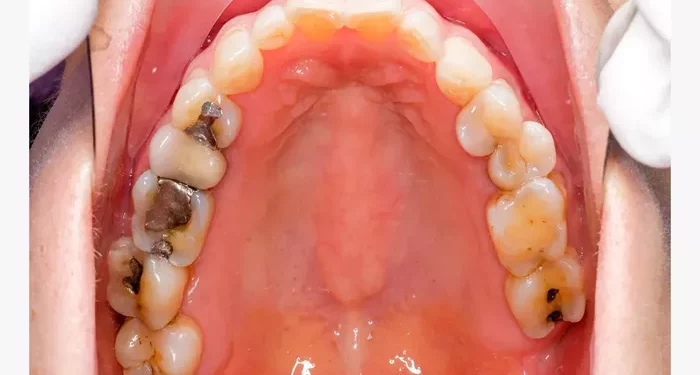

Visible holes or pits in the teeth

Discoloration or dark spots on the teeth

Amalgam fillings are made from a mixture of metals, including silver, mercury, tin, and copper. They have been used for over a century and are known for their durability and strength.

Advantages: Amalgam fillings are long-lasting, resistant to wear, and can withstand heavy chewing pressure. They are also less expensive than some other filling materials.

Disadvantages: The silver color of amalgam fillings can be less aesthetically pleasing, especially for front teeth. Additionally, some patients may have concerns about mercury exposure.